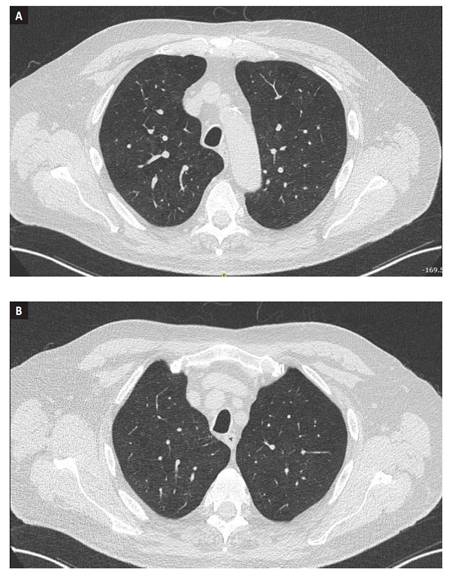

Se vuelve a interrogar al paciente, el cual refiere inicio reciente de montelukast (dos semanas previas), por episodios recurrentes de broncoespasmo considerándose posible asma superpuesta a EPOC. Se suspende manejo con inhibidor de leucotrieno y se indican pulsos de glucocorticoides por tres días con mejoría significativa de la sintomatología. Al descartar como causas, las patologías autoinmunes e infecciosas sin presentar manifestaciones asociadas a ninguna de estas entidades e inicio reciente de un medicamento con cambios agudos en la tomografía de tórax con respecto a la previa (Figura 1 y 2) y hallazgos de hemorragia alveolar difusa, se considera alta probabilidad que haya cursado con una reacción adversa al montelukast. No se realizó TACAR de control dada la mejoría clínica presentada por el paciente.

Figura 1 Tomografía simple de tórax, ventana pulmón con corte axial tres semanas previas al inicio de síntomas (A) y una semana previa de inicio de montelukast (B). Enfisema centrilobulillar más evidente en el lóbulo superior derecho, signos de hipertensión pulmonar precapilar, sin otros hallazgos en parénquima pulmonar o mediastino.